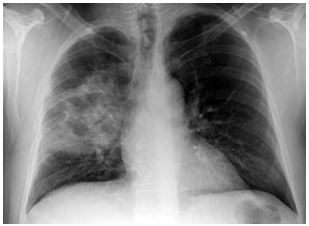

Paciente do sexo masculino, 72 anos de idade, extabagista, DPOC (GOLD II), chega ao pronto-socorro com febre, tosse purulenta, dispneia progressiva e confusão mental. Ao exame físico: PA: 82 × 50 mmHg; FC: 118 bpm; FR: 28 irpm; SpO2: 90% com cateter 3 L/min; T: 38,7 ºC; tempo de enchimento capilar de 5 s; extremidades frias. Na abordagem terapêutica inicial, o paciente recebeu ringer lactato (2.100 mL EV) em 45 minutos e antibioticoterapia de amplo espectro (piperacilina-tazobactam 4,5 g EV).

Porém, após a reposição volêmica, o paciente apresenta PA: 86 × 52 mmHg; FC: 116 bpm; saturação venosa de O2: 61%; lactato: 4,6 mmol/L (antes 4,9). Gasometria venosa: pH: 7,31; PvCO2: 46 mmHg; HCO3: 22 mEq/L. Creatinina: 2,2 mg/dL (baseline 1,0); bilirrubinas normais; leucócitos: 17.800/mm3; PCR: 22 mg/dL. Realizou-se a radiografia de tórax a seguir:

Enunciado 4482331-1 (Arquivo pessoal; imagem usada com autorização)

Qual é a intervenção hemodinâmica apropriada nesse momento?